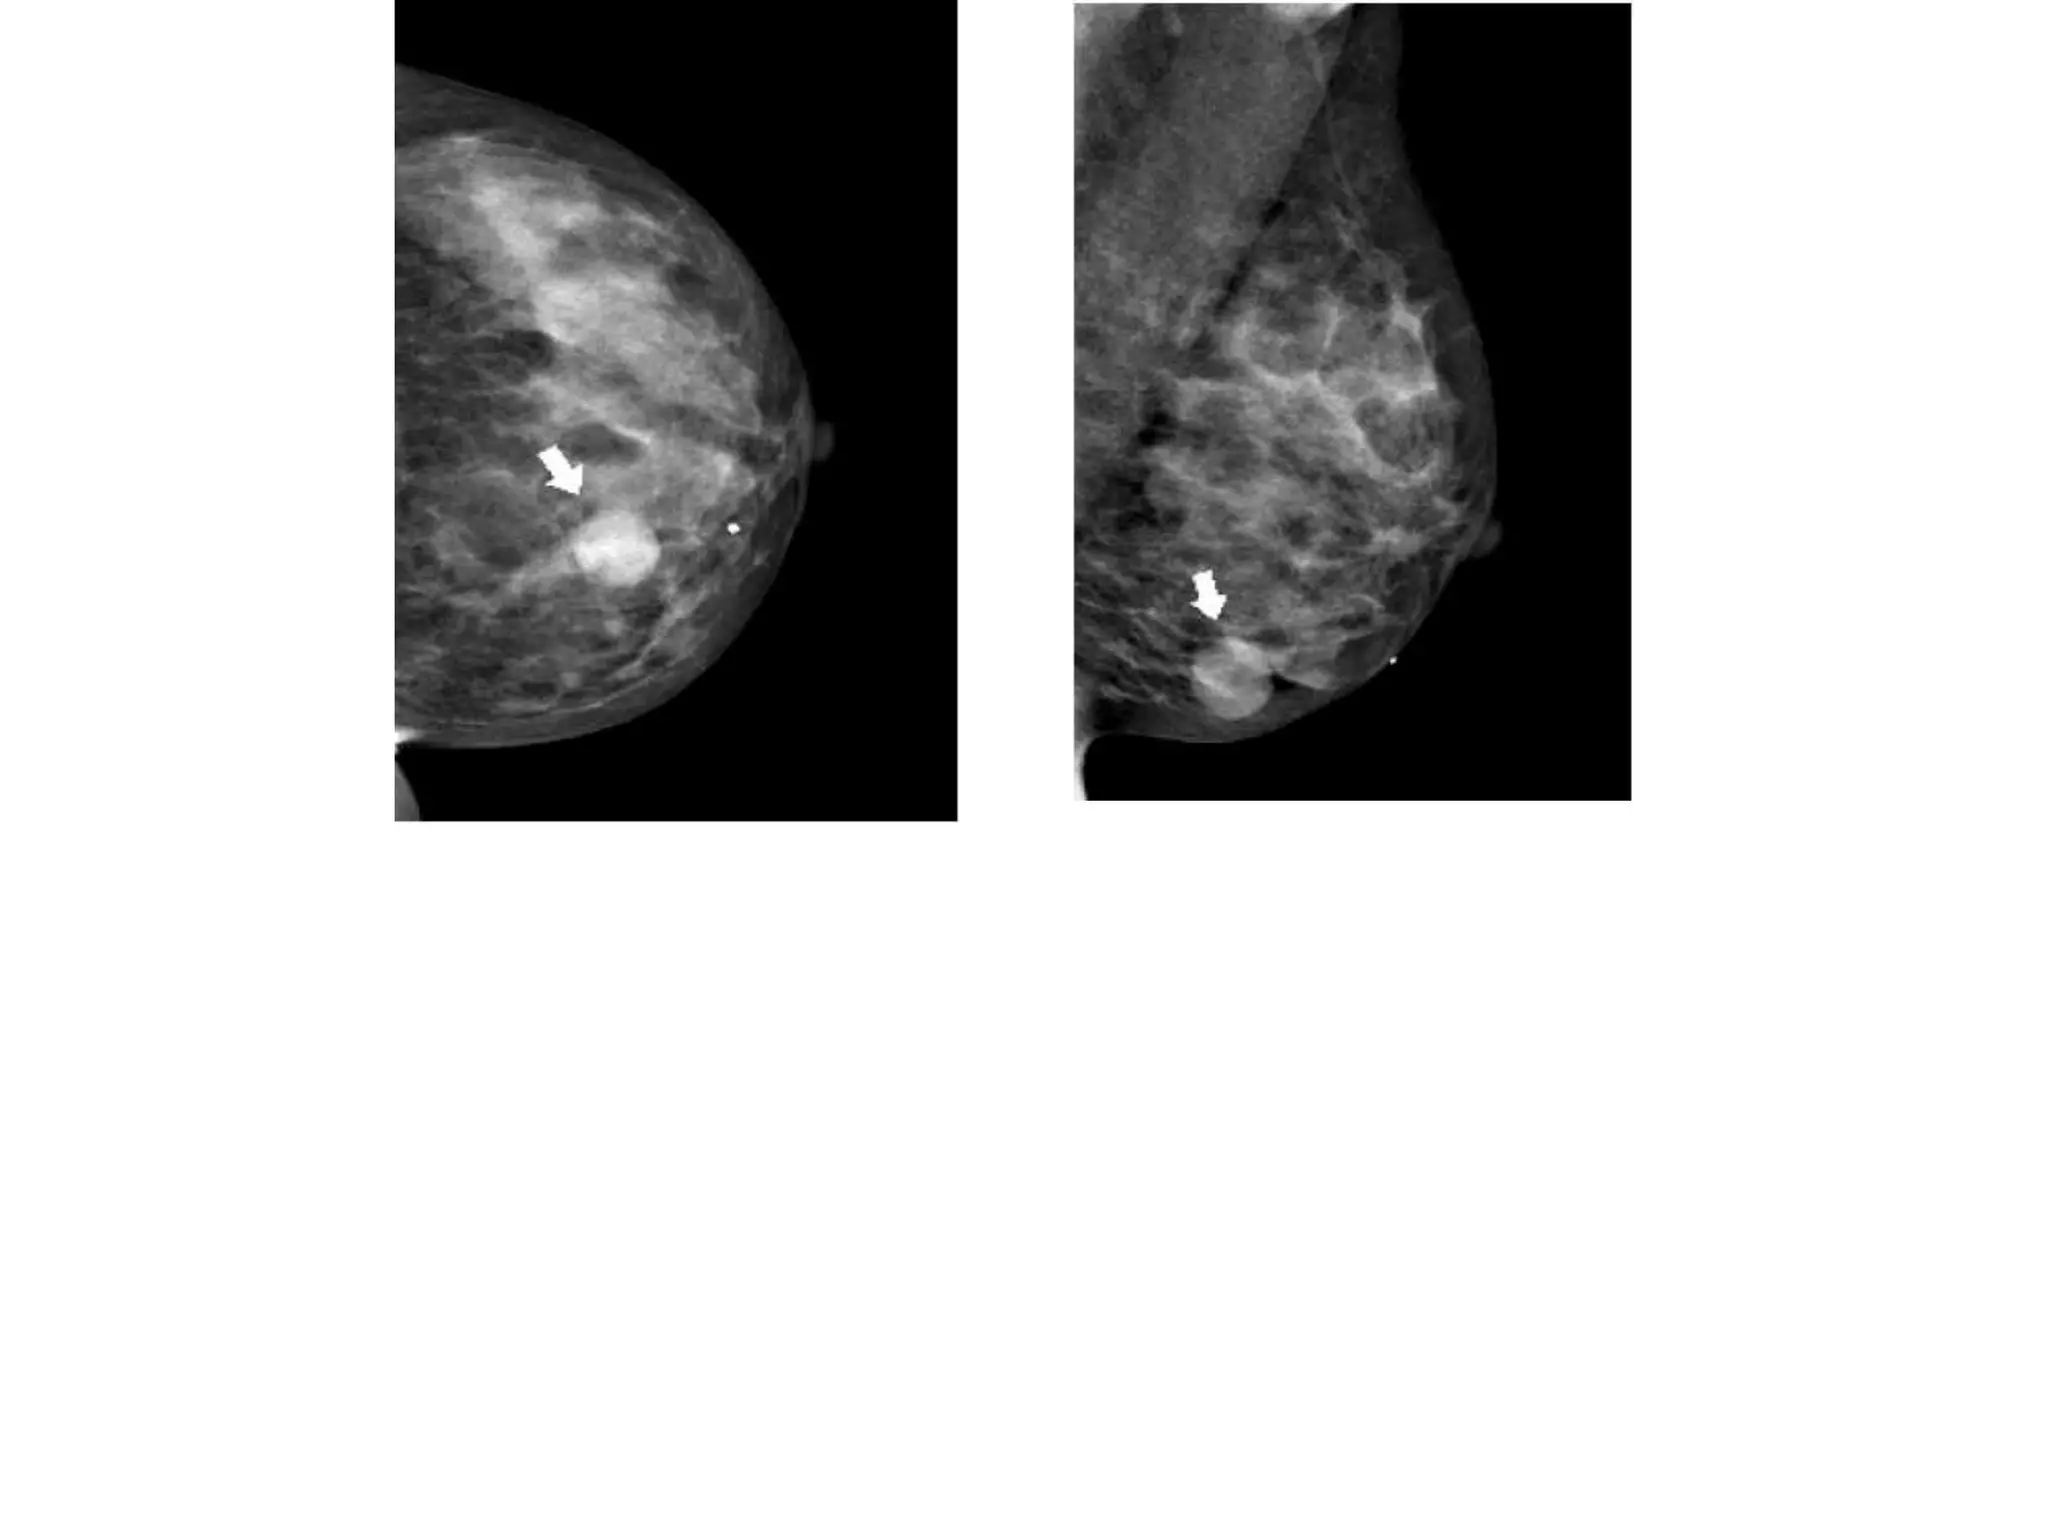

• #47 The mass isseen as a space-occupying structure with convex outward borders (arrows).Figure 2: Asymmetry seen in (a) schematic, (b) MLO views, and (c) CC views. Apotential lesion lacking the characteristics of a mass is seen only on the left CC view(arrow). A corresponding abnormality is not seen on the left MLO view.

• #49 So perform additional views.LESION SHOULD NOT BE IN THE AREA WHICH CANT BE CAPTURED IN BOTH THE VIEWS LIKE IN AXILLA NEAR CHEST WALL.For an asymmetry seen only on the MLO view, it is frequently best to go immediatelyto the straight lateral view (8). This slight shift in the orientation of breast structuresrelative to the x-ray beam is often sufficient, by the disappearance or changedFor asymmetries seen only on CC projections, the rolled view is best for determiningthe presence of a lesion (8). To obtain this view, the breast can be gently rotated aroundthe axis of the nipple and recompressed in this new orientation. Rolling the breast willdo little to obscure a true lesion, which will simply be displaced in the direction of theapplied roll. Conversely, rolling the breast in an appropriate manner will cause asummation shadow to virtually disappear because the relevant tissues will be displacedwith regard to one another. To properly determine the presence of a lesion, the directionof roll should be chosen so that the region in question is rolled toward and projectedover an area of fat and not over dense tissue, so that the lesion is not obscured. Thisrequires preliminary assessment of the fibroglandular pattern. If a true lesion is rolledinto an area of dense fibroglandular tissue, it may be obscured, leading to the erroneousconclusion that it has &quot;disappeared.&quot; Therefore, each rolled projection must be tailoredfor each patient (7). In addition, movement of a true abnormality relative to theSpot Compression View

• #50 Figure 2: Asymmetry seen in (a) schematic, (b) MLO views, and (c) CC views. Apotential lesion lacking the characteristics of a mass is seen only on the left CC view(arrow). A corresponding abnormality is not seen on the left MLO view.